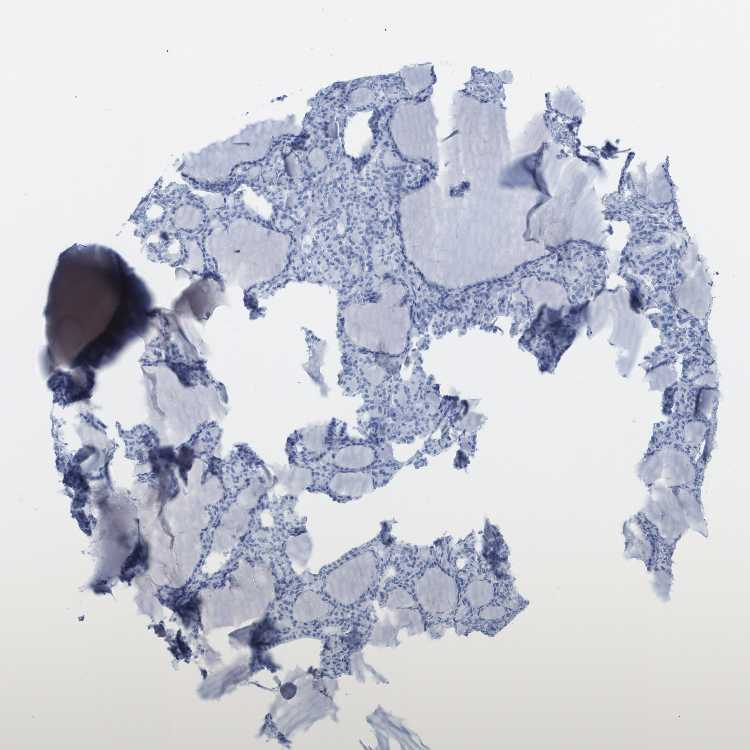

THYROID GLAND - Antibody stainingi

Antibody staining in the annotated cell types in the current human tissue is reported as not detected, low, medium, or high, based on conventional immunohistochemistry profiling in selected tissues. This score is based on the combination of the staining intensity and fraction of stained cells.

Each image is clickable and will lead to virtual microscopy that enables deeper exploration of all samples and also displays staining intensity scores, fraction scores and subcellular localization as well as patient and tissue information for each sample.

Antibody HPA016625

Glandular cells Not detected